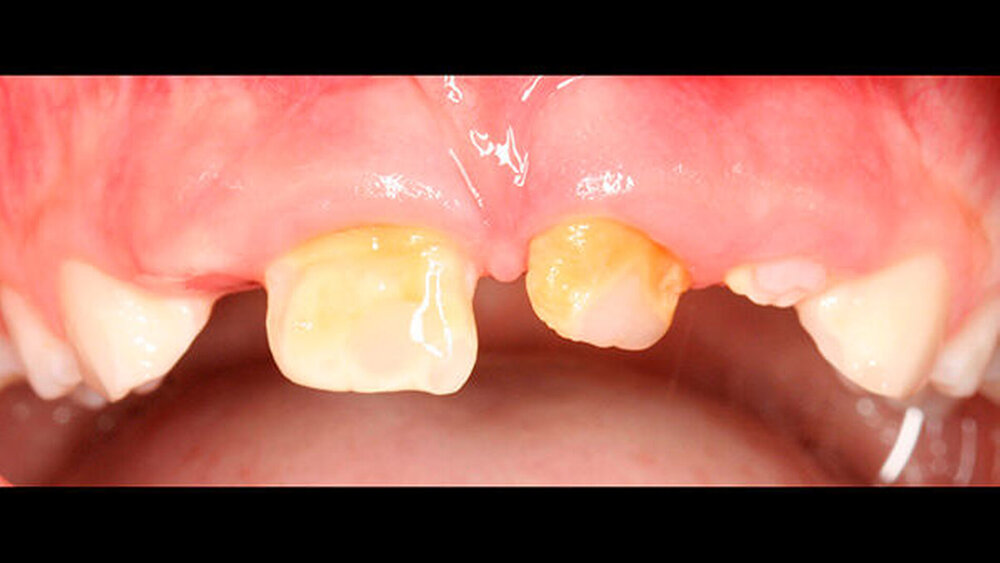

Abbildung 1 gibt einen guten Überblick darüber, dass teils mehrere Restaurationen pro Zahn durchgeführt wurden und die dazwischen verbliebenen Bereiche aus Zahnschmelz oft nur gering waren (insbesondere an den Frontzähnen). Gleichzeitig zeigt aber auch der Vergleich der kontralateralen Prämolaren, wie anfällig dieser verbliebene Schmelz für Abplatzungen war. Im Unterkiefer ist gerade an Zahn 37 deutlich zu erkennen, wie großflächig die Schmelzverluste sein können, wenn auch die Restauration nicht mehr intakt oder vorhanden ist.

a) Dentinogenesis imperfecta. Da alle Zähne betroffen sind, ist von einer genetisch bedingten Fehlbildung auszugehen. Die Zähne der Patientin weisen zudem eine veränderte Farbe auf. Darüber hinaus sind Abplatzungen des Schmelzes vorzufinden. Trotzdem liegt keine Dentinogenesis imperfecta vor. Die Abplatzungen sind größtenteils geringfügig und zunächst oberflächlich, das heißt nicht unmittelbar bis zum Dentin. Die Farbänderung der Zähne entspricht nicht dem klassischen Bild einer Dentinogenesis imperfecta (siehe auch Abbildungen 3 und 4).

Zudem kann es immer wieder zu Abplatzungen des verbliebenen Schmelzes kommen, so dass der entsprechende Zahn eine neue Restauration benötigt, oder die schon vorhandene ausgedehnt werden muss (siehe auch Abbildungen 1 bis 3) [Crawford et al., 2007].